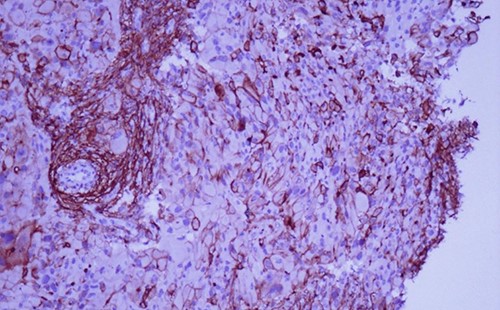

A 42-year-old man with no clinical history presented with a non-ulcerated polypoid skin nodule of the front side of the chest wall, which had grown over a period of 6 months, measuring 1,8 × 1,5 cm (Fig. 1). The lesion was removed completely with tumor-free margins of 0,5 cm. Microscopically, the tumor was composed of a diffuse infiltrate of polygonal cells with abundant granular cytoplasm and vesicular nuclei (Figs 2 and 3). There was no atypia or necrosis. The average mitotic count was one to two per 10 high-power field. Immunohistochemistry showed positive expression for CD10, CD68 and ALK with negative staining for CK AE1/AE3, CD34, S100 and HMB45 (Figs 4 and 5). No recurrence was noted during follow-up of 6 months.

Immunohistochemistry shows consistent negative expression of S100, smooth muscle actin, desmin, cytokeratin, CD34, HMB 45 and melan-A. CD10 and CD68 are usually positive [2, 3]. ALK antibody can be positive with weak to moderate cytoplasmic expression [6].

Immunohistochemistry reveals positivity for CD 10 (magnification at ×400).